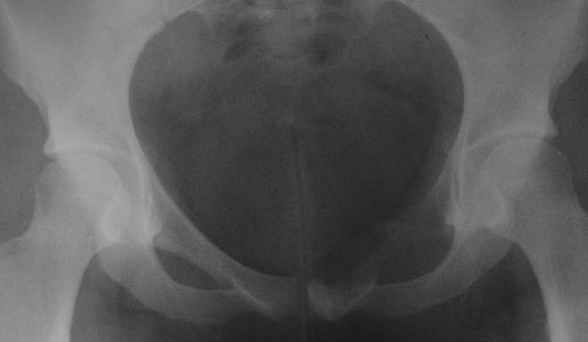

ОБК лонной кости

пациентка 20 лет, в сентябре 2005 года почувствовала боли в паху. На снимках заподозрили остеомиелит, лечили антибиотиками без эффекта. К онкологу попала в январе2006. Биопсия в марте 2006 - остеобластокластома. Местные онкологи от операции отказываются.

Вопрос с планом лечения (надо ли замещать деффект и чем) и где оперироваться (опыт подобных операций). В приложении рентгенограммы в динамике (2005 сентябрь, декабрь, 2006 апрель).